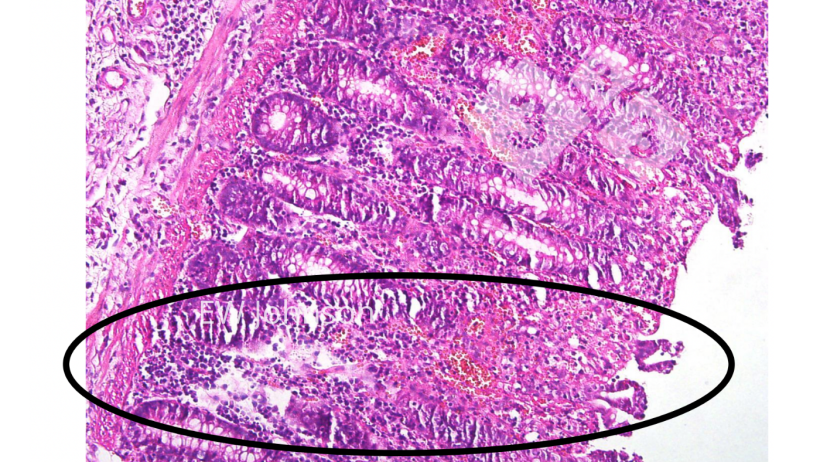

No exame histopatológico é observada uma vasculite generalizada com infarto, hemorragia e trombose em diversos orgãos, particularmente no pulmão, baço, nódulos linfáticos, rins, cérebro e intestino. Há uma destruição linfóide massiva nos nódulos linfáticos e baço e vacuolização dos macrófagos alveolares. É frequente a necrose e a ulceração do epitélio do cólon (foto 4). Foto 4. Trombose vascular, infarto, ulceração na mucosa do cólon.